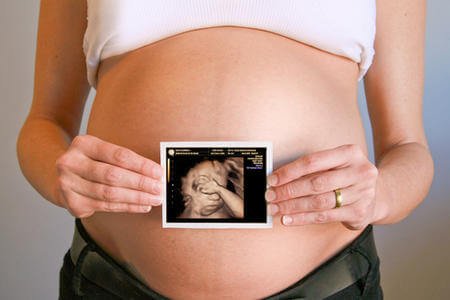

A ciência demonstrou que, durante a gravidez, seu bebê sente as mesmas coisas que você e com a mesma intensidade.

Se você chora de tristeza, seu bebê vai experimentar na própria pele esse estado emocional. Ele vai sentir como se essa tristeza e essa angústia fossem dele.